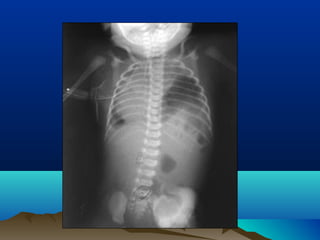

Hirschsprung’sHirschsprung’s

Abdominal X-ray (HSD)Abdominal X-ray (HSD)

HSDHSD

Barium EnemaBarium Enema

showing 3 differentshowing 3 different

zoneszones :-:-

-Spastic lower zone-Spastic lower zone

-funnel shaped middle-funnel shaped middle

zonezone

-markedly dilated proximal-markedly dilated proximal

(normal) colon(normal) colon